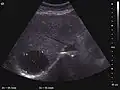

They can be single or multiple, with variable size, generally less than 20 mm (congenital). Rarely, sizes can reach several centimeters, leading up to the substitution of a whole liver lobe (acquired, parasitic). They may be associated with renal cysts; in this case the disease has a hereditary, autosomal dominant transmission (von Hippel Lindau disease).

The ultrasound appearance is a well defined lesion, with very thin, almost unapparent walls, without circulatory signal at Doppler or CEUS investigation. The content is transonic suggesting fluid composition. The presence of membranes, abundant sediment or cysts inside is suggestive for parasitic, hydatid nature. Posterior from the lesion the acoustic enhancement phenomenon is seen, which strengthens the suspicion of fluid mass. They typically displace normal liver vessels but no vascular or biliary invasion occurs.

Hydatid liver cyst. Diagnostic criteria are the presence of membranes and sediment inside.